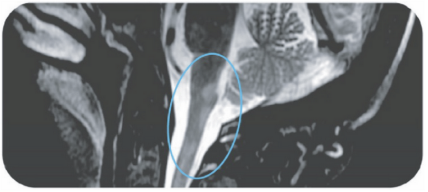

Area postrema syndrome is a core clinical characteristic of NMOSD that can appear both at disease onset and throughout the clinical course7

- The spectrum of NMOSD symptoms is broad and includes nausea, vomiting, and intractable hiccups7,8

- 4 out of 10 NMOSD attacks of the area postrema include all 3 symptoms7

- Due to symptom severity, ~80% of patients with NMOSD-related area postrema syndrome are hospitalized7